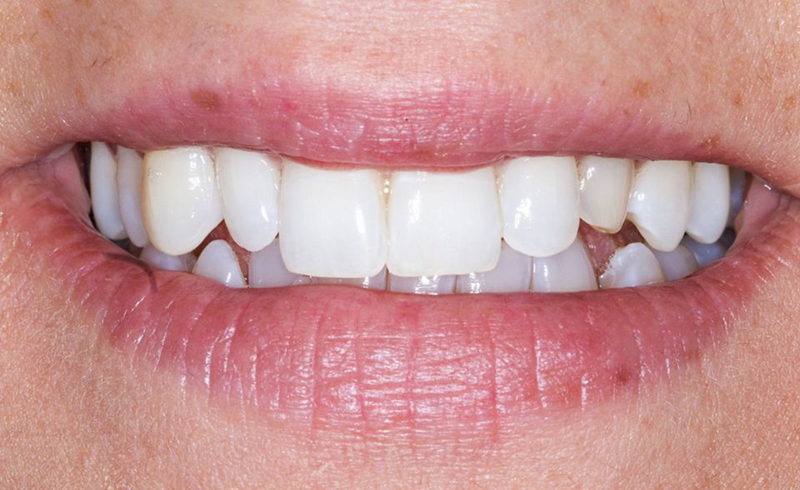

口外检查中,面部评价显示面部对称、比例匀称。微笑分析显示中线矢状面与微笑中线重合,上切牙和尖牙的暴露率为90%(图1)。微笑还显示侧切牙形状不同,与对侧恒尖牙相比,左上乳尖牙更短、更窄、颜色更黄(图2-4)。

Fig. 2: Frontal view of the patient’s smile.